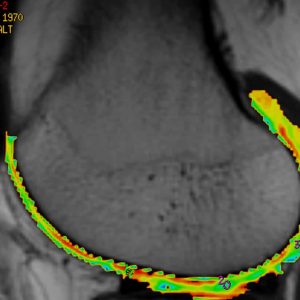

La resonancia magnética (RM) es un estudio médico no invasivo que utiliza campo magnético (1.5 teslas) y ondas de radio para obtener imágenes detalladas del interior del cuerpo. Permite visualizar órganos, tejidos blandos, huesos y estructuras internas con gran precisión, sin usar radiación ionizante. Es una herramienta clave para diagnosticar enfermedades neurológicas, musculoesqueléticas y otras condiciones internas.